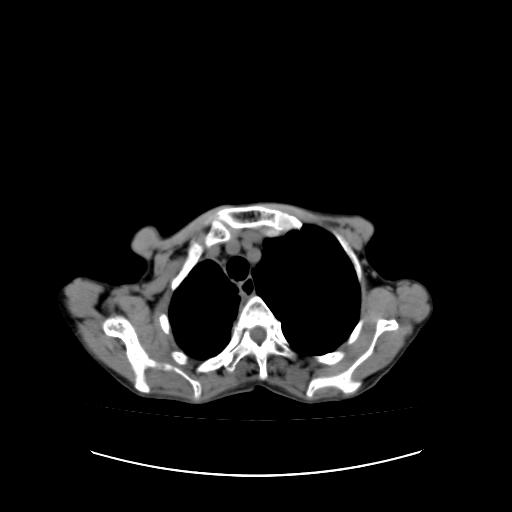

标题: CT16930:女 59 胸痛6个月 胸水脱落细胞学见瘤细胞 [打印本页]

可见多发肺内病灶,且胸膜病灶较多有圆球状而非丘状,多考虑胸膜转移瘤伴胸腔积液,右侧胸廓缩小固定,且部分病灶呈丘状,尚不除外恶性胸膜间皮瘤伴肺内转移

右侧胸膜增厚,局部呈结节状增厚,右侧胸腔少量积液。双肺未见确切肿块影。纵隔未见淋巴结肿大。气管、支气管通畅。考虑右侧胸膜间皮瘤(恶性?)可能性大。不除外癌性胸膜炎。

恶性胸膜间皮瘤伴肺内转移可能性大;或胸膜、肺内均为转移瘤,左肺下叶亦见多发小结节影。

右侧胸廓塌陷,右侧胸膜广泛增厚并见多发胸膜结节,右侧少量胸腔积液并包裹。

右侧广泛胸膜增厚,局部呈结节状增厚,右侧胸腔少量积液。双肺未见确切肿块影。纵隔未见淋巴结肿大。气管、支气管通畅。考虑右侧胸膜间皮瘤(恶性?)可能性大。支持!

右侧胸膜转移瘤,原发灶可能就在在右肺,另外建议检查右侧乳腺.

右胸腔结节均考虑来自胸膜(部分来源于叶裂),考虑胸膜间皮瘤或转移瘤.